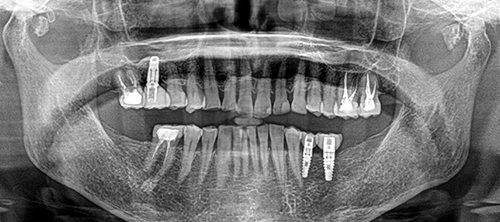

治療内容 ・インプラント

・セラミック修復

治療期間 9ヶ月

治療費用 250万円

元々全体的に歯と歯の間がすいていて食渣が挟まりやすかったが、インプラントを入れることで奥歯にしっかりしたサポートが回復され、歯の隙間が自然と詰まり、物詰まりも軽減することができた。

After